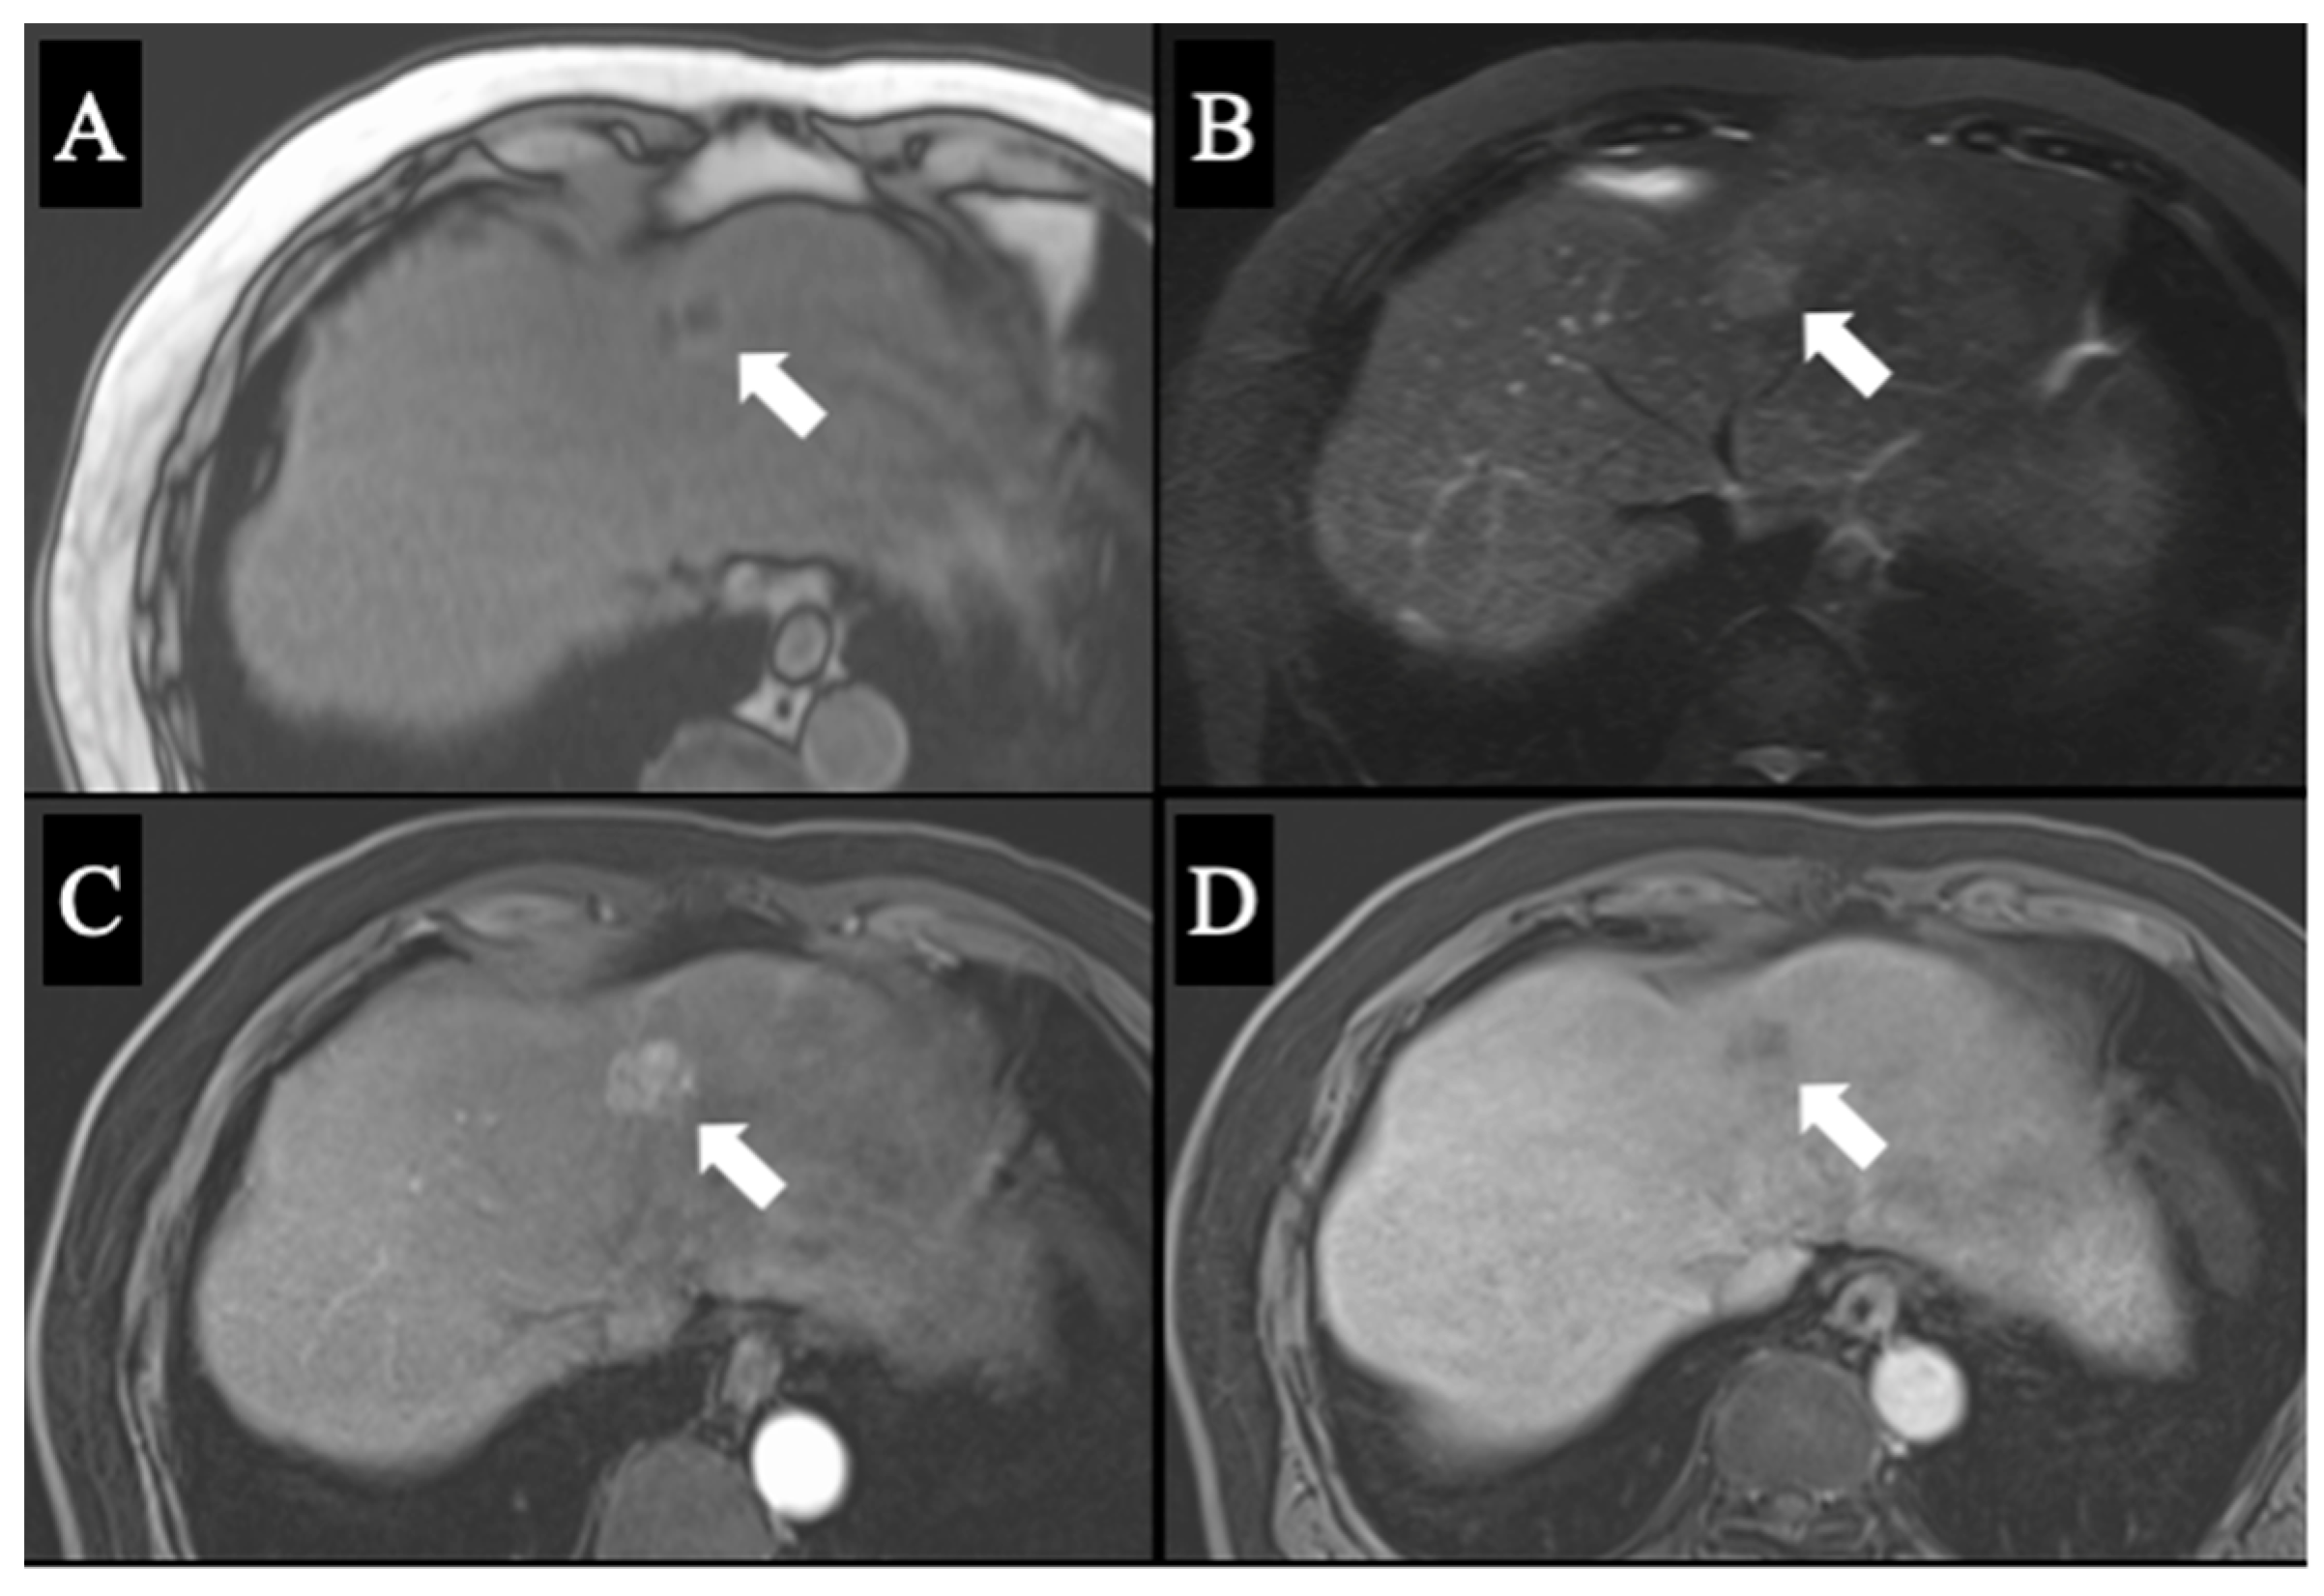

2. Case Report